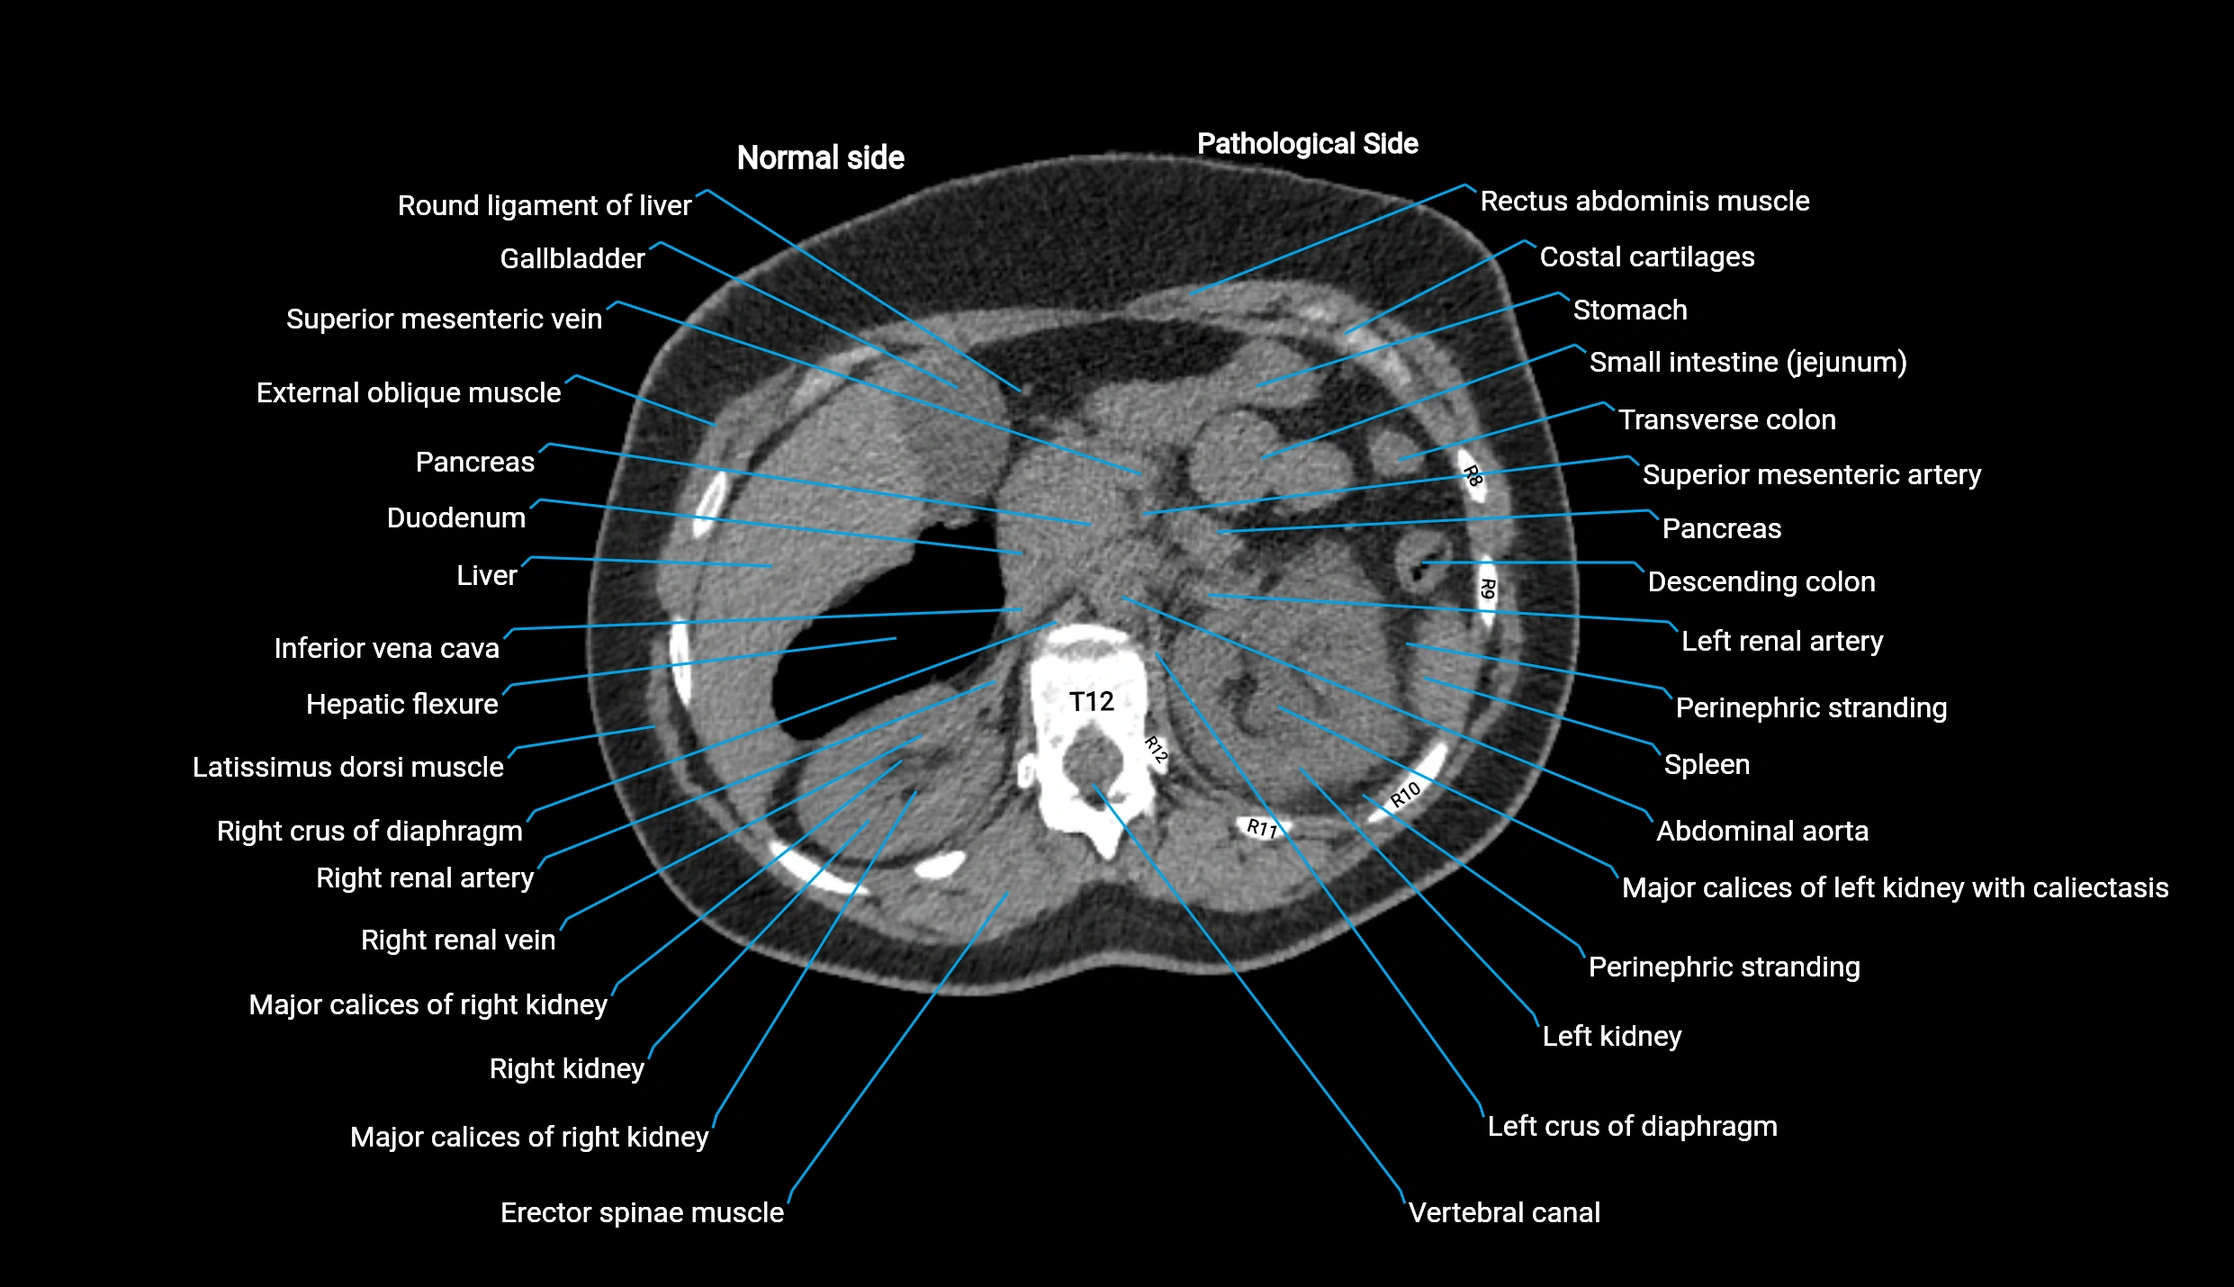

CT image

image